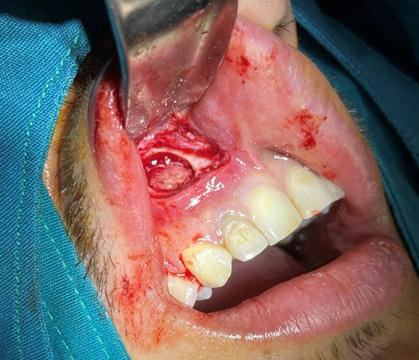

Issuu converts static files into: digital portfolios, online yearbooks, online catalogs, digital photo albums and more. Sign up and create your flipbook.